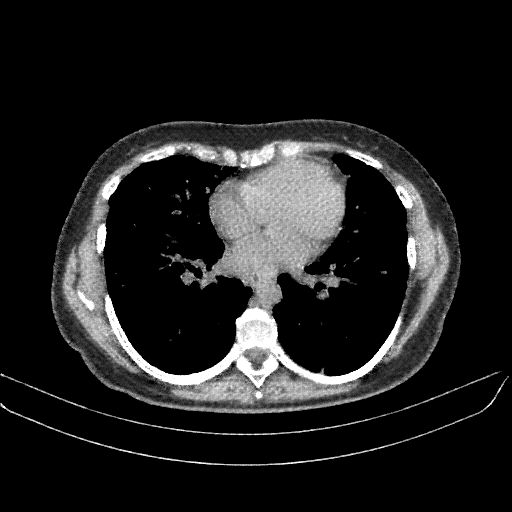

Original VENOUS CT scan

No window - Raw intensity values

Lung window (WL -600, WW 1500 β†’ Low βˆ’1350, High +150)

Mediastinum window (WL 40, WW 400 β†’ Low βˆ’160, High +240)